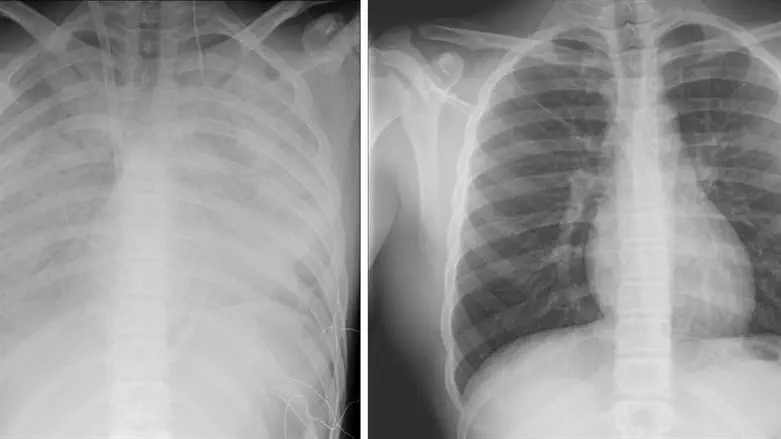

הנער הועבר למרכז שניידר מבית החולים קפלן, במצב של קריסת ריאות. מבירור רפואי מקיף שערכו בבית החולים קפלן עלה כי מצבו של הנער נגרם, ככל הנראה, כתוצאה מעישון של סיגריות אלקטרוניות.

לדברי פרופ' עובדי דגן, מנהל היחידה לטיפול נמרץ לב: "הנער התקבל ליחידה לטיפול נמרץ לב במצב קשה מאד כשריאותיו אינן מתפקדות, והוא זקוק לתמיכה מלאה של מכשיר אקמו. אנו מטפלים בו ומקווים מאד לשיפור במצבו בימים הקרובים. הנזק שנגרם, ככל הנראה, מעישון של הסיגריות האלקטרוניות הוא נזק עצום. אנו קוראים לכל ההורים, מנעו את המקרה הבא".